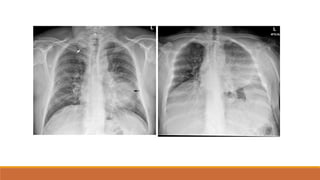

TDMP TỰ DO

PHIM THẲNG ĐỨNG

•TÙ GÓC SƯỜN HOÀNH

•BÓNG MỜ VÙNG THẤP XÓA BỜ VÒM HOÀNH VỚI

GIỚI HẠN TRÊN LÀ ĐƯỜNG CONG DAMOISEAU

•ĐẨY TRUNG THẤT VỀ PHÍA ĐỐIDIỆN

•XẸP PHỔI THỤ ĐỘNG (+/-)

•THAY ĐỔI THEO TƯ THẾ

TDMP lượng ít

TDMP lượng vừa

TDMP lượng nhiều

TDMP ÁP LỰC, ĐẨY TRUNG THẤT VỀ PHÍA ĐỐIDIỆN